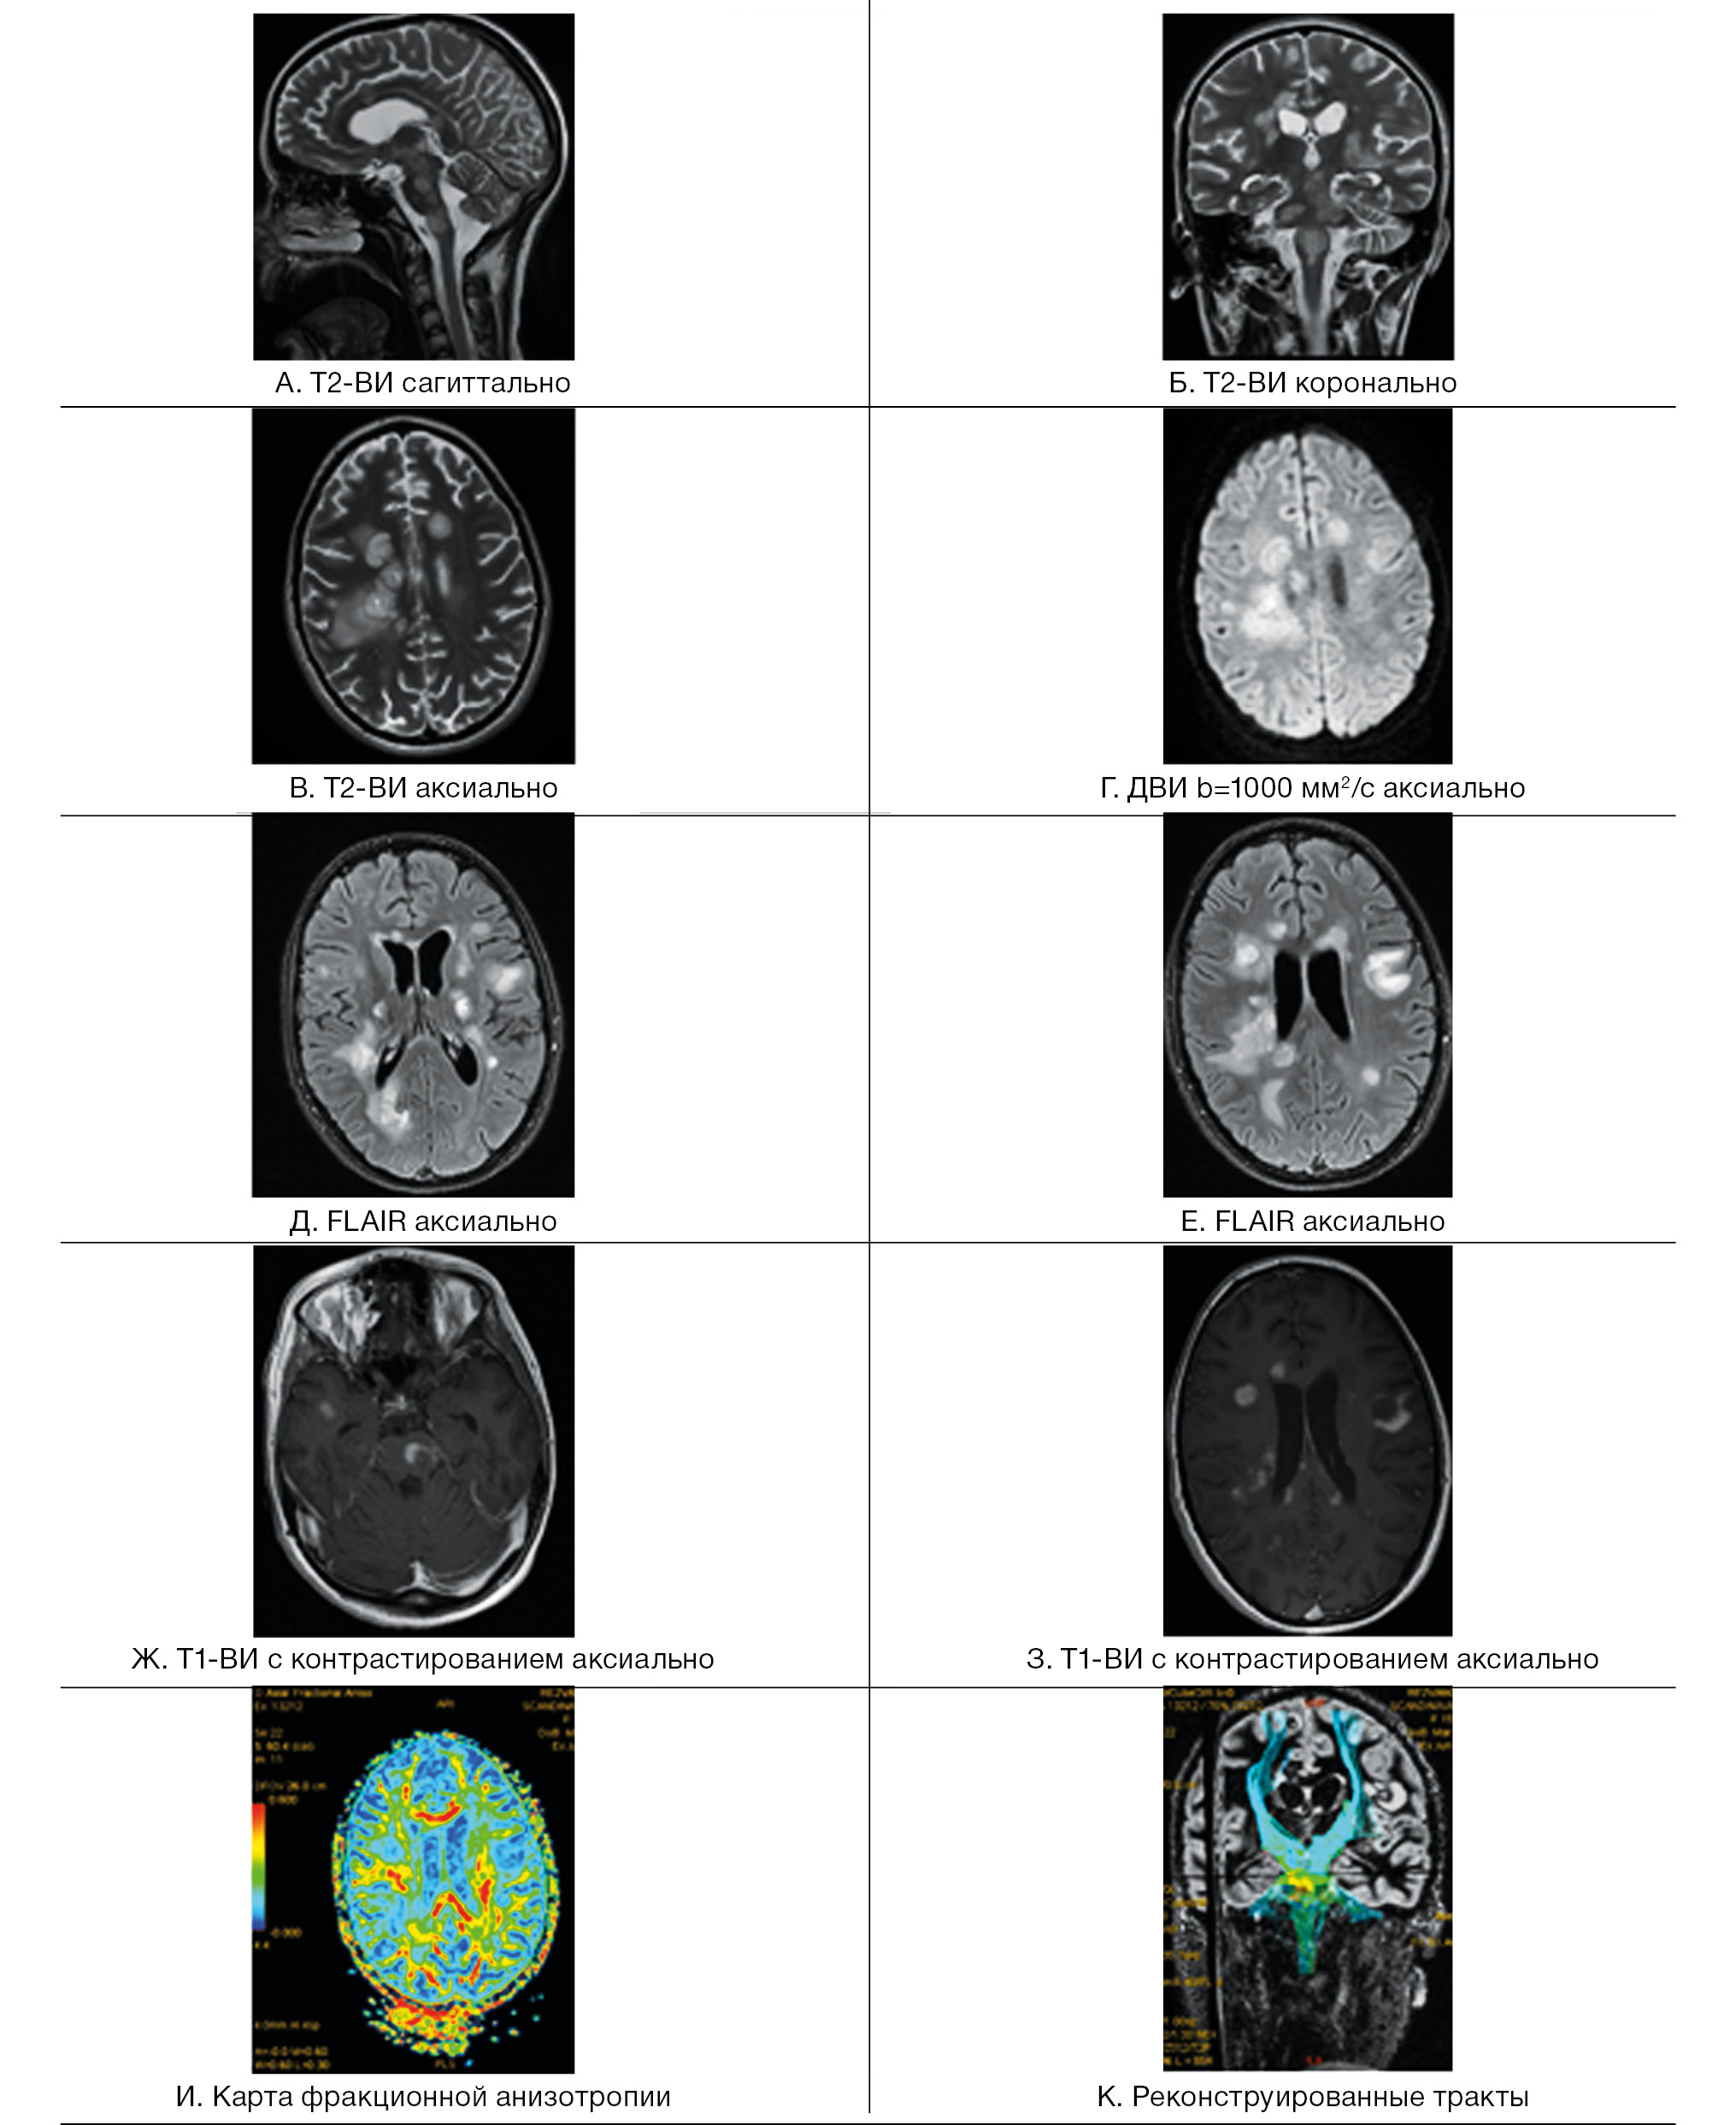

Термины «ромбоэнцефалит» и «стволовой энцефалит» используются для обозначения одного и того же поражения, вовлекающего субтенториальные структуры — ствол мозга и мозжечок [22]. Это состояние воспалительной природы может быть инфекционным, аутоиммунным или паранеопластическим. Инфекционный ромбоэнцефалит может наблюдаться при любом вирусном или бактериальном энцефалите; в 50% случаев регистрируется вовлечение супратенториальных структур [37]. Наиболее часто стволовой энцефалит вызывается энтеровирусами 71-го типа, листериями, вирусом простого герпеса [38, 39]. МРТ-находки при этой патологии неспецифичны. Очаги обычно множественные, асимметричные, Т2-гиперинтенсивные и не всегда накапливающие контрастное вещество в режиме Т1 (рис. 2).

Рис. 2. Пациент М., 9 лет. МРТ: вирусный энцефалит, острый период течения заболевания. Этиология — герпес II типа (IgM с крови)

Примечание. А–И — последовательность Т2-flair. Имеется поражение зрительных бугров, глубокого перивентрикулярного и субкортикального белого вещества лобных и теменных долей, задних отделов моста, глубоких отделов гемисфер мозжечка; Д, Е — с повышением сигнала за счет цитотоксического отека в стволе головного мозга при факторе взвешенности В1000 на диффузионно-взвешенных изображениях и признаками ограничения диффузии (измеряемый коэффициент диффузии снижен до 0,4×10-3 мм2/с); Ж — при внутривенном контрастировании без нарушения гематоэнцефалического барьера в зоне поражения; З — при выполнении DTI МР-трактографии фракционная анизотропия в стволе снижена до 0,19; И — пики NAA и Cho практически одинаковые по высоте, т.е. косвенный признак снижения нейрональной плотности в зоне поражения, пик лактата (маркер анаэробного гликолиза) неубедителен на фоне шума (данные Детского научно-клинического центра инфекционных болезней ФМБА, Санкт-Петербург).

Острый диссеминированный энцефаломиелит в большинстве случаев — монофазное и мультифокальное воспалительное заболевание [38, 53, 54]. Стволовые очаги по данным МРТ невозможно дифференцировать от таковых при рассеянном склерозе, однако у таких пациентов чаще выявляются повреждения на уровне среднего мозга, кроме того, они более симметричны, билатеральны, чем при рассеянном склерозе [38, 55]. Билатеральное симметричное вовлечение мозжечка, базальных ядер, таламуса и относительная сохранность мозолистого тела подтверждают диагноз острого диссеминированного энцефаломиелита (рис. 3).

Рис. 3. Пациентка Р., 15 лет. МРТ: острый диссеминированный энцефаломиелит с трансформацией в рассеянный склероз

Примечание. Множественные перивентрикулярные, субкортикальные крупные очаги с нечеткими и неровными контурами, накапливающие контрастное вещество фрагментарно, преимущественно по краям (нарушение гематоэнцефалического барьера), с незначительным повышением МР-сигнала на ДВИ 1000 с/мм2 (отечные изменения). Внутренняя структура очагов неоднородная. Визуализируется поражение ствола мозга, спинного мозга и мозжечка. Ограничение фракционной анизотропии на уровне очагов (до 0,2) и снижение плотности реконструируемых трактов на этом уровне (данные Детского научно-клинического центра инфекционных болезней ФМБА России, Санкт-Петербург).